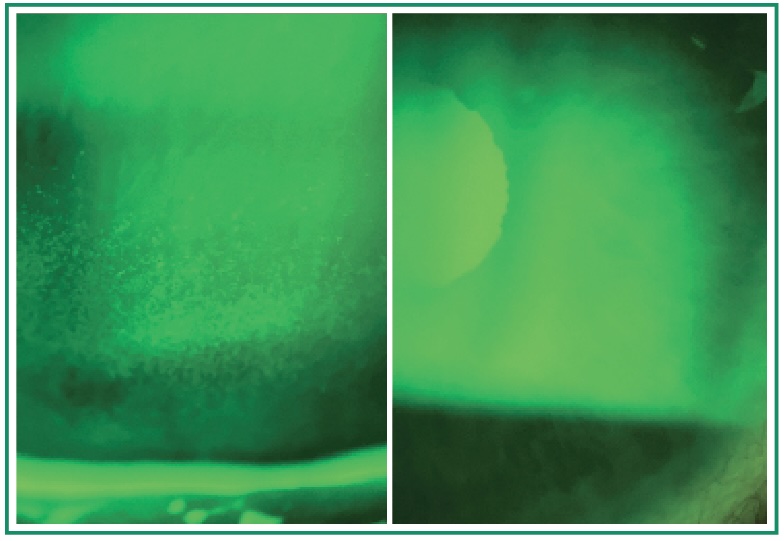

• Ocular surface distress

Punctate keratitis, follicular conjunctivitis, or reduced tear break-up time suggests the “drop-induced” pathology may be causing more harm than the glaucoma itself. Early intervention preserves the conjunctiva for both current quality of life and future glaucoma surgical success.

Presentation: On three topical medications (latanoprost, dorzolamide/timolol, brimonidine), IOP marginally controlled at 18-19 mmHg. Severe ocular surface disease with Grade 3 punctate keratitis, severe discomfort, and fluctuating vision affecting reading – her primary hobby.